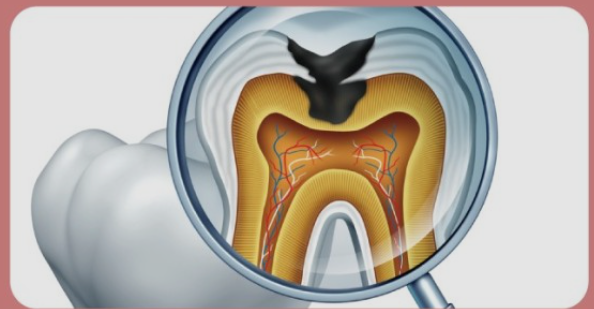

외상 또는 충치로 인해 치아의 치수(신경)가 손상되었거나 염증이 생기게되면 통증이 느껴지게 되요. 문제가 생긴 신경을 방치하게 되면 일상생활에 지장이 있을 정도로 통증이 심해지며 염증이 점점 커지기 때문에 손상되었거나 염증이 생긴 치수를 제거하는 것이 치아 신경치료이에요.

치아마다 모양이 다르고 그 안에 있는 시경은 더욱 복잡하게 얽혀 있어요. 신경관이 막혀 신경을 제거하지 못한 경우도 있고 신경치료를 하였으나 신경조직이 남아있는 경우도 있어요. 치아 상태에 따라 재 신경치료 or 치아 재식술을 통해 치아의 기능을 회복할 수 있어요.